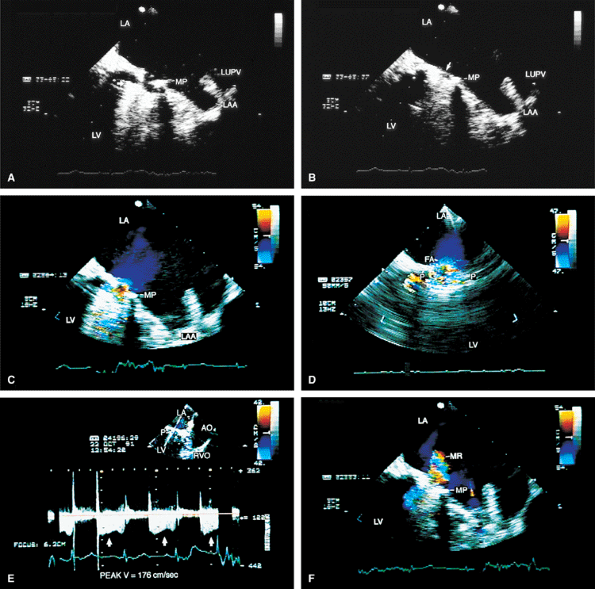

FIGURE 5.36. Medtronic-Hall prosthesis: abscess/aortopulmonary fistula. A–E. The modified four-chamber and five-chamber views demonstrate a portion of the aortic prosthesis (arrow) protruding into the left ventricular outflow tract (LVOT). The anterior leaflet of the mitral valve (MV) shows two perforations, one at the base (1) and the other in the midportion (2). Mitral regurgitation (MR) jets are seen moving into the left atrium (LA) through these perforations (MR-1, MR-2) and also from the coaptation area of the mitral leaflets (MR-3). B. The diastolic frame shows the prosthesis in contact with the body of the anterior mitral leaflet (AML) in the area of the perforation. E. Both valvular (V) and paravalvular (P) aortic regurgitation (AR) are noted. F,G. Modified aortic short-axis views demonstrate the fistulous connection between the aortic root (A) and the main pulmonary artery (PA) through an abscess cavity (A3). Two other abscess cavities (A1, A2) are also noted. H,I. Abscess cavity A2 is well demonstrated. J,K. The relationship of the abscess cavity A1 to the superior vena cava (SVC) during transverse (J) and longitudinal (K) plane examinations is demonstrated. L–N. Longitudinal plane examination shows the abscess cavity A3. Its communication with the PA is seen in N. AO, aorta; LV, left ventricle; PML, posterior mitral leaflet; RA, right atrium; RV, right ventricle; RVO, right ventricular outflow tract; SVC, superior vena cava. (Reproduced with permission from Chen CH, Nanda NC, Fan PH, et al. Transesophageal echocardiographic diagnosis of aortopulmonary fistula. Echocardiography 1993;10:85–90. ) |